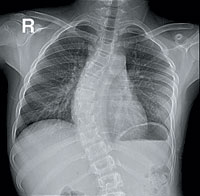

أضاف مستشفى الملك خالد الجامعي تقنية جديدة من خلال جهاز (فبتر) الذي يساعد على تعديل انحراف العمود الفقري لدى الأطفال دون سن التاسعة حيث يسمح هذا الجهاز للعمود الفقري بالنمو بعد التعديل على خلاف الأجهزة الأخرى. |

وأكد الأستاذ المشارك بكلية الطب واستشاري

...>>>...